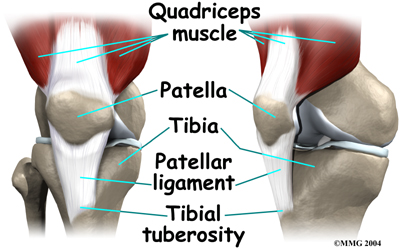

The knee joint is made up of the other end of the femur and the end of the shin bone. The knee cap, or patella, is also part of the knee joint.

Overuse syndromes are common in active adolescents. Stress fractures of the foot, patellofemoral joint problems, and are examples of overuse syndromes.